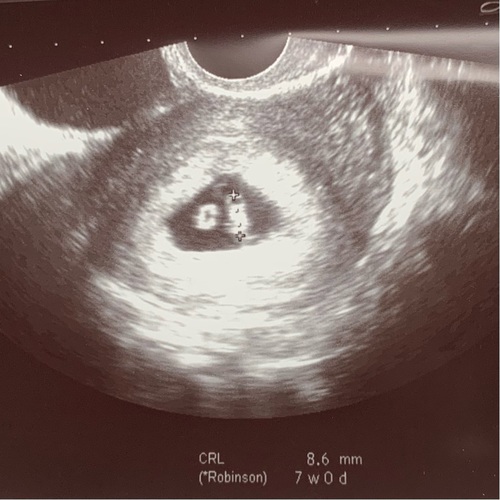

Dit was ons dochtertje met 7+2 weken zwangerschap. Ze was toen 11mm en haar hartje klopte al op een mooi tempo. Veel succes donderdag!